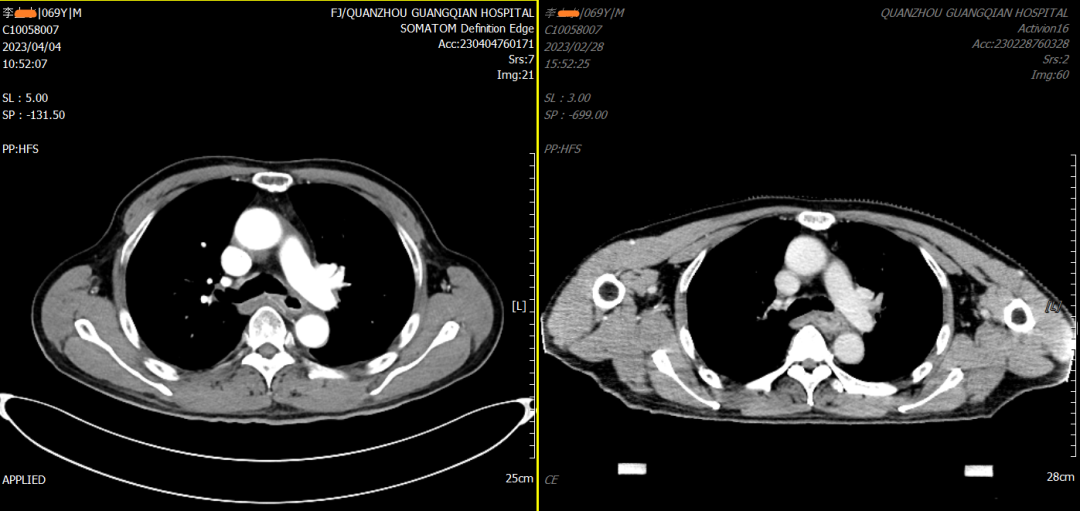

李先生及家屬經(jīng)深思熟慮后,決定在我院行精準(zhǔn)同步放化療。放療一區(qū)林玉宗主任攜其診療團(tuán)隊,共同討論制定治療方案,并多次與浙江省腫瘤醫(yī)院專家進(jìn)行探討,制定了最佳的個體化精準(zhǔn)治療方案。整個治療過程很順利,且不良反應(yīng)較小。治療結(jié)束后復(fù)查CT提示食管病灶明顯消退。李先生的病情得到了很好的控制,身體狀況日漸恢復(fù),生活質(zhì)量持續(xù)好轉(zhuǎn)。

▲治療前后對比圖